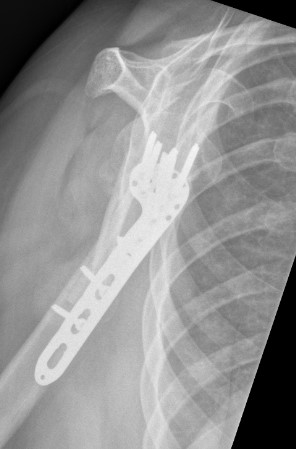

ORIF with locking plate

Apply plate

- lateral to biceps with single cortical screw in oblique hole

- check fluoroscopy - avoid having plate too high

- keep head out of varus to avoid cutout

- long inferomedial screws / kickstand screws

- locking screws

Long proximal humerus plates

Synthes 3.5 mm LCP Periarticular proximal humerus plate surgical technique PDF